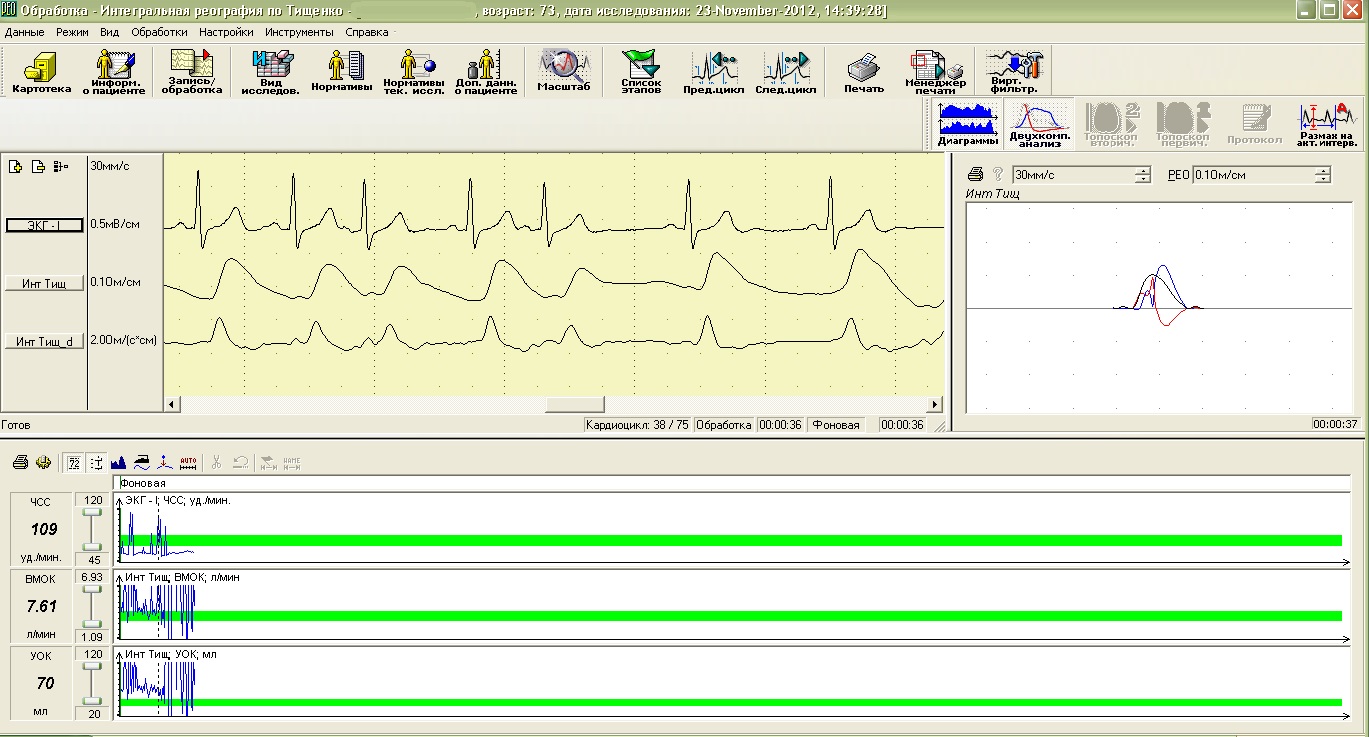

Параллельно с инструментальной регистрацией функций мозга желательно проверить состояние сосудов головного мозга, в которых, как правило, с возрастом регистрируются изменения лимфовенозного или микроциркуляторного отделов кровообращения, а порой, и состояния магистральных артерий. Особенно важно проверить функциональные особенности работы сердца (даже при отсутствии жалоб) и определить тип кровообращения, что в дальнейшем позволит врачам разрабатывать методики для поддержания оптимального функционального состояния и сосудов, и работы сердца.

Оценка функциональных особенностей работы сердца

Исследование центральной гемодинамики, интегральная реография по Шрамеку